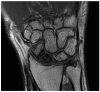

Distal radioulnar joint (DRUJ) instability is a complex condition that can severely affect forearm function, causing pain, limited range of motion, and reduced strength. This review aims to consolidate current knowledge on the diagnosis and management of DRUJ instability, emphasizing a new classification system that we propose. The review synthesizes anatomical and biomechanical factors essential for DRUJ stability, focusing on the interrelationship between the bones and surrounding soft tissues. Our methodology involved a thorough examination of recent studies, incorporating clinical assessments and advanced imaging techniques such as MRI, ultrasound, and dynamic CT. This approach allowed us to develop a classification system that categorizes DRUJ injuries into three distinct grades. This system is intended to be practical for both clinical and radiological evaluations, offering clear guidance for treatment based on injury severity. The review discusses a range of treatment options, from conservative measures like splinting and physiotherapy to surgical procedures, including arthroscopy and DRUJ arthroplasty. The proposed classification system enhances the accuracy of diagnosis and supports more effective decision making in clinical practice. In summary, our findings suggest that the integration of advanced imaging techniques with minimally invasive surgical interventions can lead to better outcomes for patients. This review serves as a valuable resource for clinicians, providing a structured approach to managing DRUJ instability and improving patient care through the implementation of our new classification system.